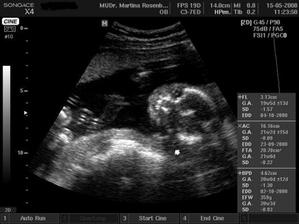

15.5. na kontrole vše v pořádku a asi opravdu budeme holčička, váhu máme 360 g a měříme 16 cm od temene hlavičky po prdelku. Příští kontrola 12.6. a o týden později 3D ultrazvuk...............